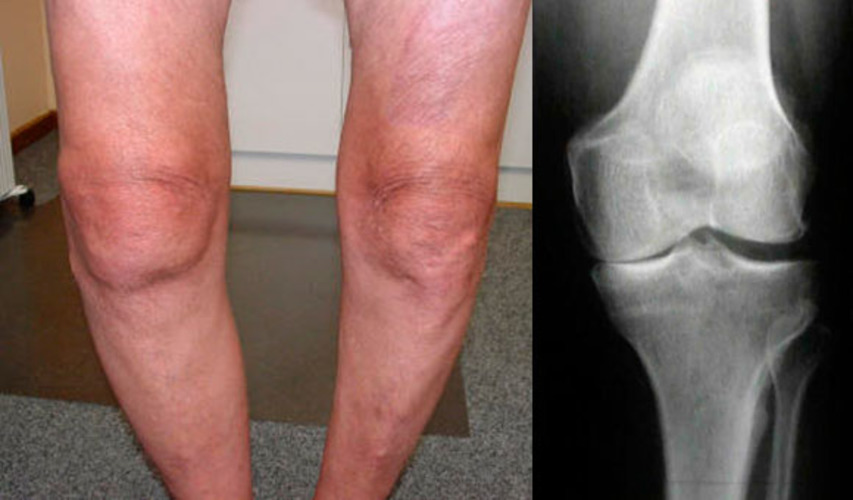

Έτσι φαίνεται μια υγιής και επώδυνη

άρθρωση. Με την ηλικία, ο ιστός του χόνδρου της άρθρωσης καταστρέφεται, παραμορφώνεται

και αραιώνεται. Αυτό μπορεί να επηρεάσει την υγεία σας, να οδηγήσει σε πόνο, ή ίσως αυτή

η διαδικασία επιδείνωσης έχει ήδη ξεκινήσει.- Τι μπορεί να βλάψει τις αρθρώσεις;

Αυτές οι φωτογραφίες δείχνουν εκφυλιστικές αλλαγές στις αρθρώσεις και πόσο μπορούν να επηρεάσουν την ποιότητα ζωής.

Άνδρας 53 ετών, άρθρωση του γόνατος. Μείωση του πάχους του χόνδρου ιστού, η οποία οδηγεί σε τραύμα στις δομές των οστών και αυτό οδηγεί σε αναπηρία σε ΟΛΕΣ ΤΙΣ ΠΕΡΙΠΤΩΣΕΙΣ, και τέτοιοι ασθενείς χρειάζονται ιδιαίτερη προσοχή.